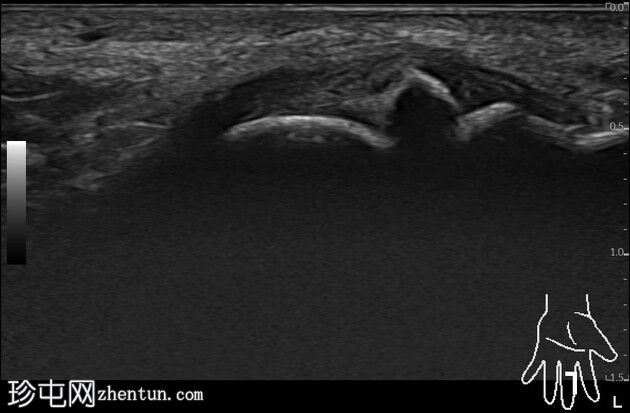

中指近端指间关节桡侧副韧带背侧/外侧纤维完整,无撕脱。韧带掌侧纤维显示中节指骨基底部骨性撕脱。桡侧副韧带本身完整。尺侧副韧带和近端指间关节掌侧板正常。伸肌腱中央腱和侧束以及屈肌腱均正常。

既往X线片(无法获取,无版权)显示中节指骨基底部掌侧桡侧骨撕脱。超声检查显示桡侧副韧带完整。骨撕脱累及掌侧纤维远端止点。